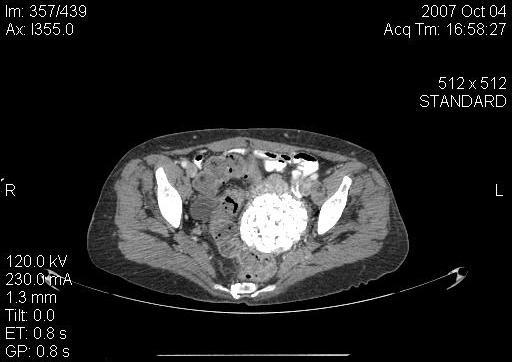

Isquemia mesentérica: Aguda y crónica